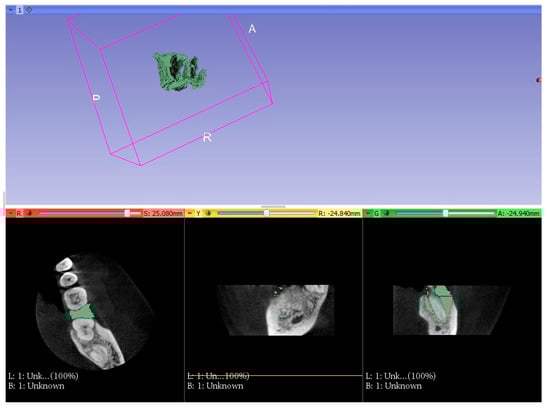

| Number of Tooth | 36 | 36 | 37 | 36 | 36 | 27 | Average Volume B/A (mm³) |

| Volume before treatment (mm³) | 654.4 | 650 | 498 | 300 | 220 | 205 | |

| Volume after treatment (mm³) | 309 | 260 | 220 | 140 | 110 | 115 | 421.23/192.3 |

| Change in percent (%) | 52.8 | 60 | 65 | 53 | 50 | 44 |

| Number of Tooth | 46 | 47 | 36 | 37 | 16 | 27 | Average Volume B/A (mm³) |

| Volume before treatment (mm³) | 287.3 | 450 | 650 | 700 | 300 | 520 | |

| Volume after treatment (mm³) | 207.1 | 310 | 400 | 580 | 245 | 360 | 484.55/350.4 |

| Change in percent (%) | 28 | 31 | 38 | 17 | 18 | 30.7 |

| Group | Amount of Teeth | Average | SD | ST p | M-W p |

|---|---|---|---|---|---|

| 1 | 6 | 192.3 | 83.0 | ||

| 2 | 6 | 350.4 | 133.1 | 0.033 | 0.037 |